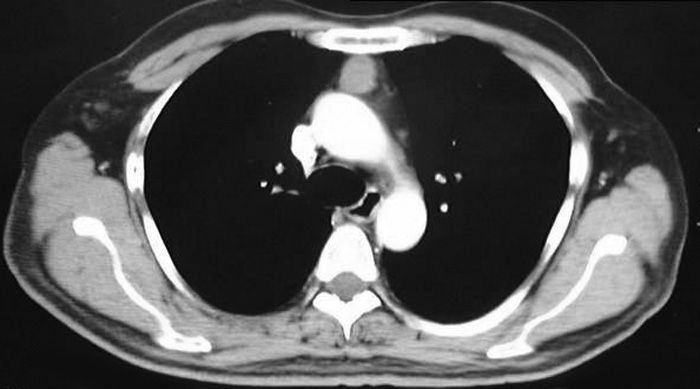

VATS thymectomy for thymoma is generally confined to small intrathymic and encapsulated tumours (Figures 11 and 12, Video 5) as there are oncological concerns of possible breach of the tumour capsule with the risk of tumour seeding. When performing VATS thymomectomy a modified no touch technique is used to minimize the risk of capsular breakage and tumour seeding, which are:

a.Only well encapsulated tumours screened on CT scan thorax are ideal for VATS.